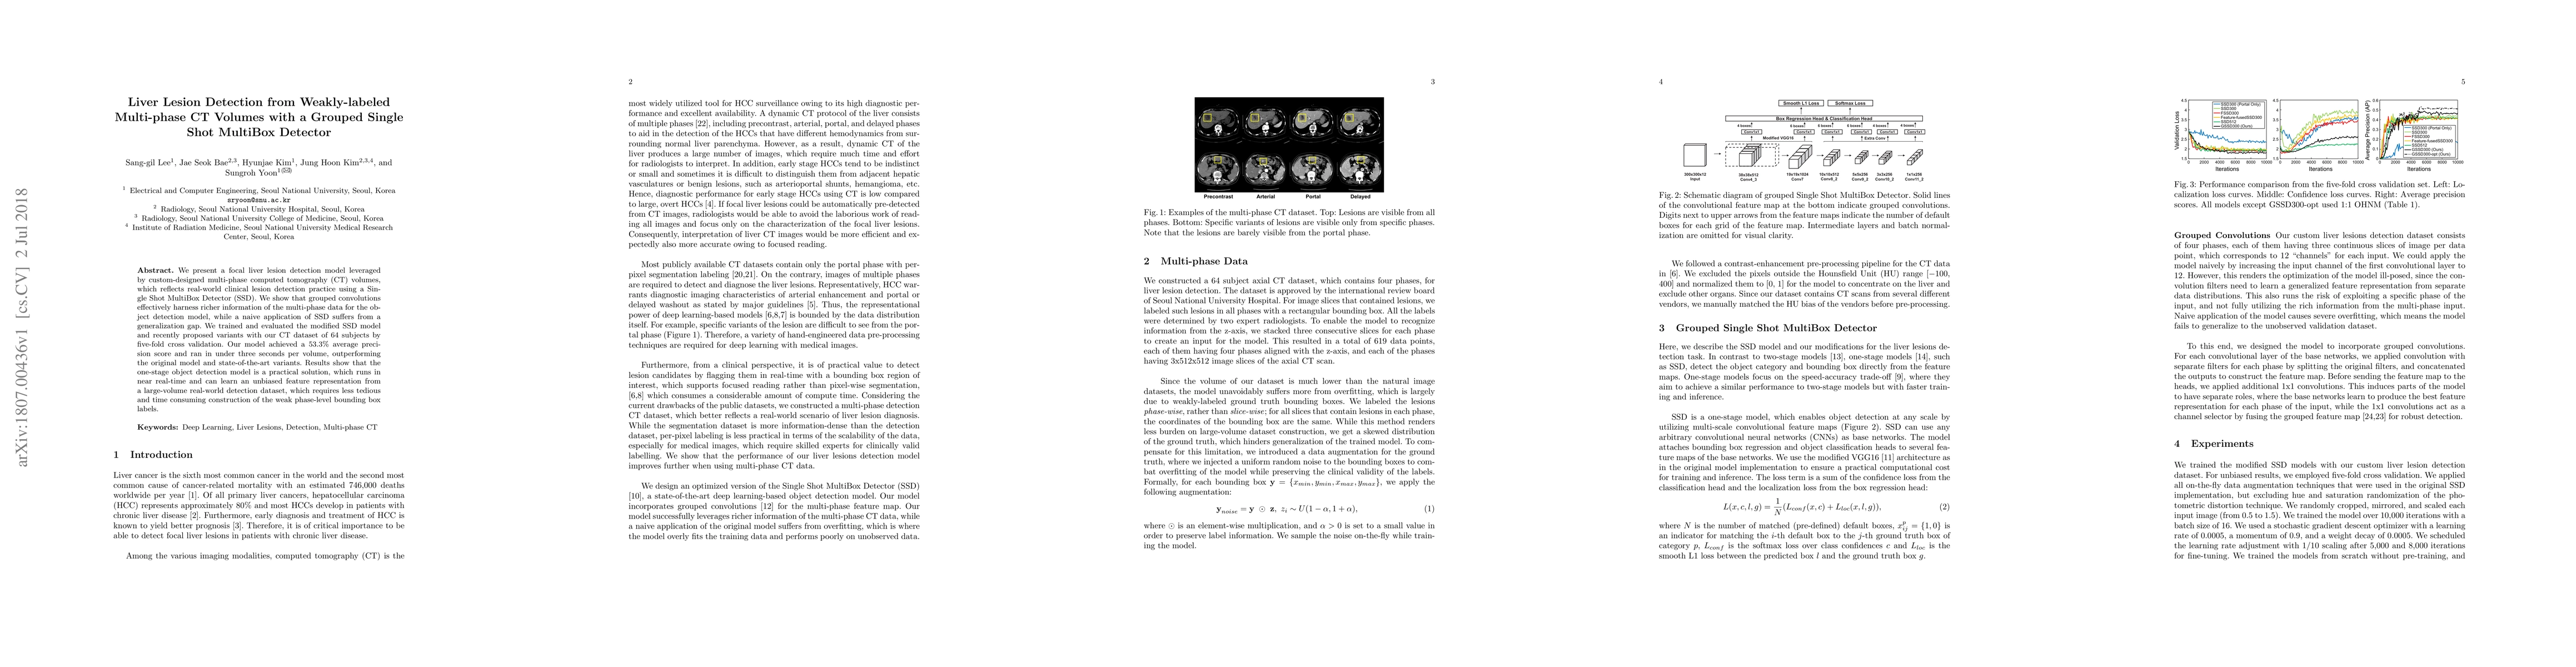

We present a focal liver lesion detection model leveraged by custom-designed multi-phase computed tomography (CT) volumes, which reflects real-world clinical lesion detection practice using a Single Shot MultiBox Detector (SSD). We show that grouped convolutions effectively harness richer information of the multi-phase data for the object detection model, while a naive application of SSD suffers from a generalization gap. We trained and evaluated the modified SSD model and recently proposed variants with our CT dataset of 64 subjects by five-fold cross validation. Our model achieved a 53.3% average precision score and ran in under three seconds per volume, outperforming the original model and state-of-the-art variants. Results show that the one-stage object detection model is a practical solution, which runs in near real-time and can learn an unbiased feature representation from a large-volume real-world detection dataset, which requires less tedious and time consuming construction of the weak phase-level bounding box labels.